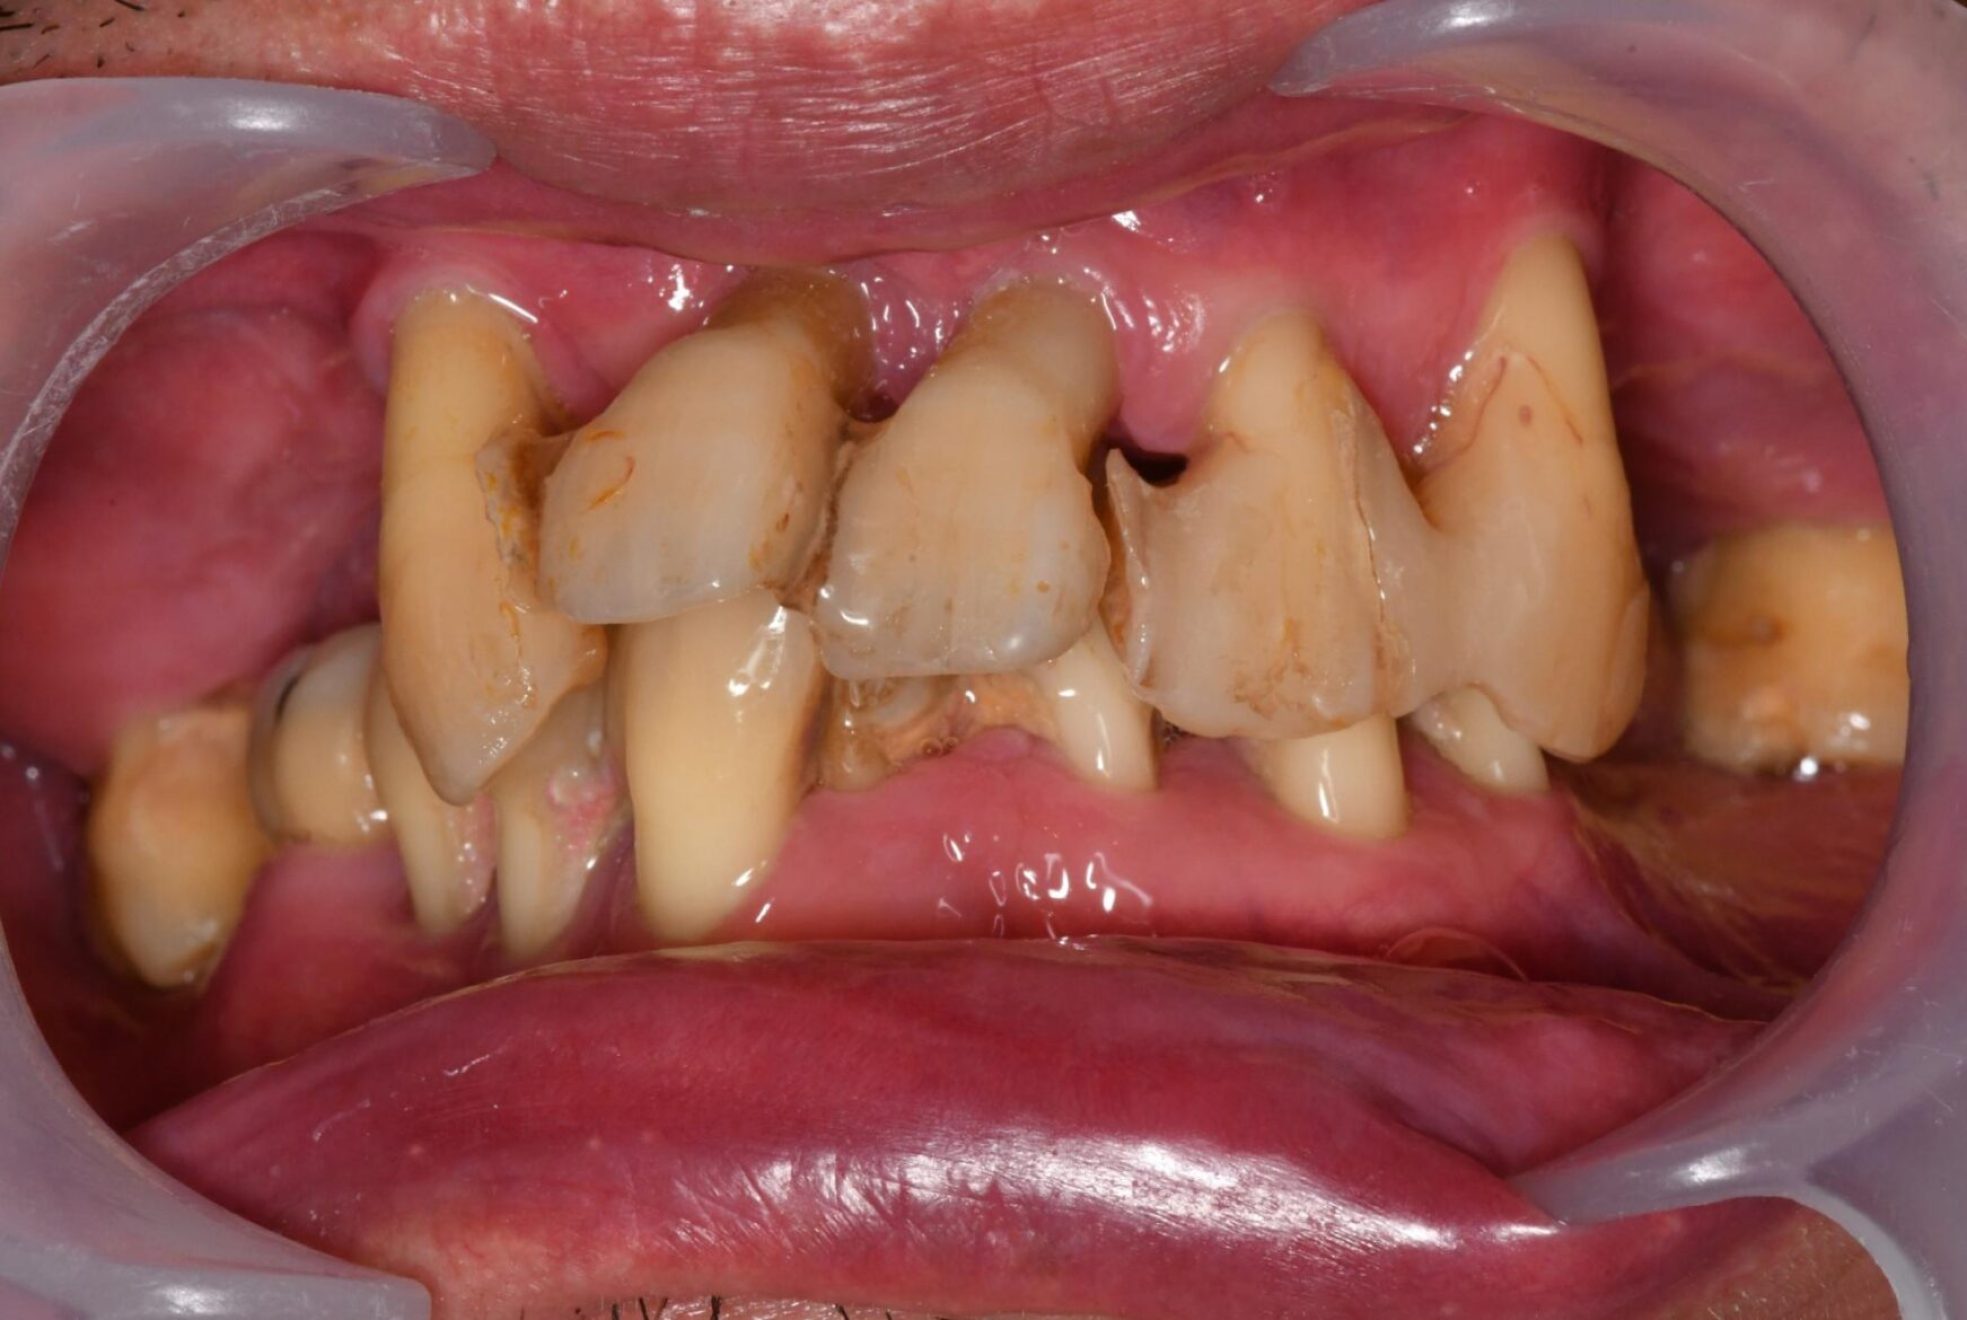

上下All-on-4

上顎:オールオン4ザイゴマ4本

下顎:オールオン4

Before

After